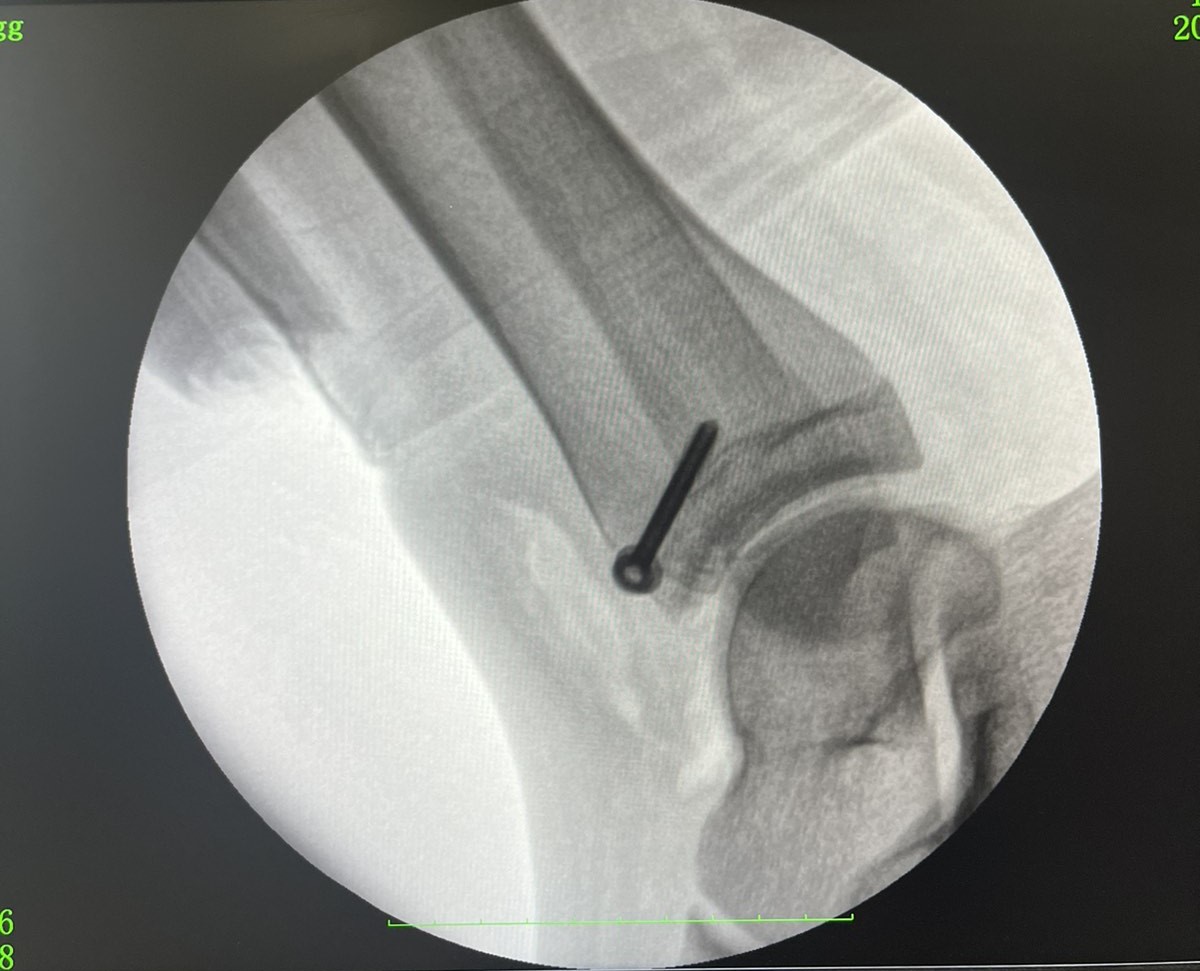

Пацієнтку госпіталізували в ортопедо-травматологічний центр лікарні з переломом великогомілкової кістки, якому було вже два тижні. За допомогою рентгенографії вдалося визначити, що це був рідкісний перелом Тілло.

За словами медиків, цей вид перелому виникає внаслідок зайвої зовнішньої ротації в гомілковостопному суглобі. Він призводить не тільки до деформації кістки, а й до пошкодження передньо-нижньої великогомілкової зв’язки.

Перелом Тілло (фото: facebook.com/RivneODL)